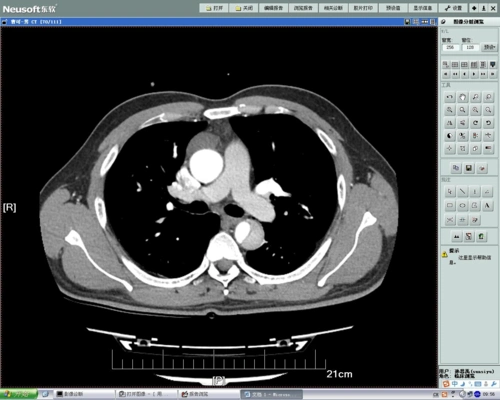

ct影像 主动脉夹层